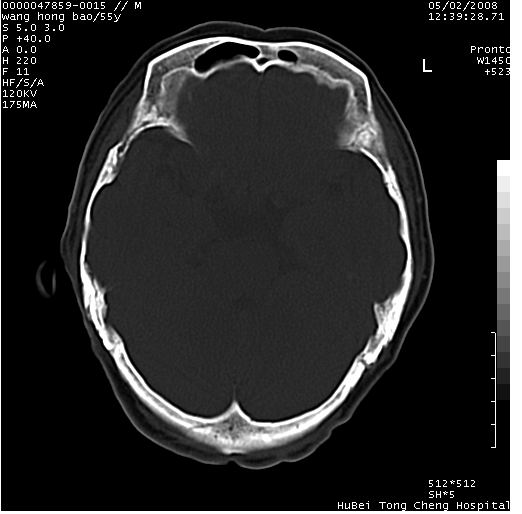

以下是引用dyqct在2008-5-3 23:36:00的发言:[br]桥前池区可疑蛛网膜囊肿。其它未见明显异常。建议做mri。

以下是引用qiushi在2008-5-4 10:10:00的发言:[br]鞍上池前缘突出影为双侧额叶直回;箭头所指为双侧正常之人字缝.[br]桥前池区可疑表皮样囊肿或蛛网膜囊肿,必要时mri

以下是引用zjzjr在2008-5-4 14:50:00的发言:[br]桥前池区可疑蛛网膜囊肿。其它未见明显异常。建议做mri。